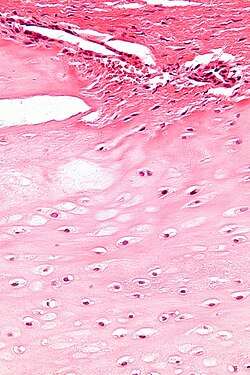

Cartilage

Chondroma

| Chondroma | ctyologically benign cells | equally spaced nests | usu. diaphysis | benign / DDx: chondroma, well-diff. chondrosarcoma | IHC / bone marrow cavity chondroma = enchondroma | |